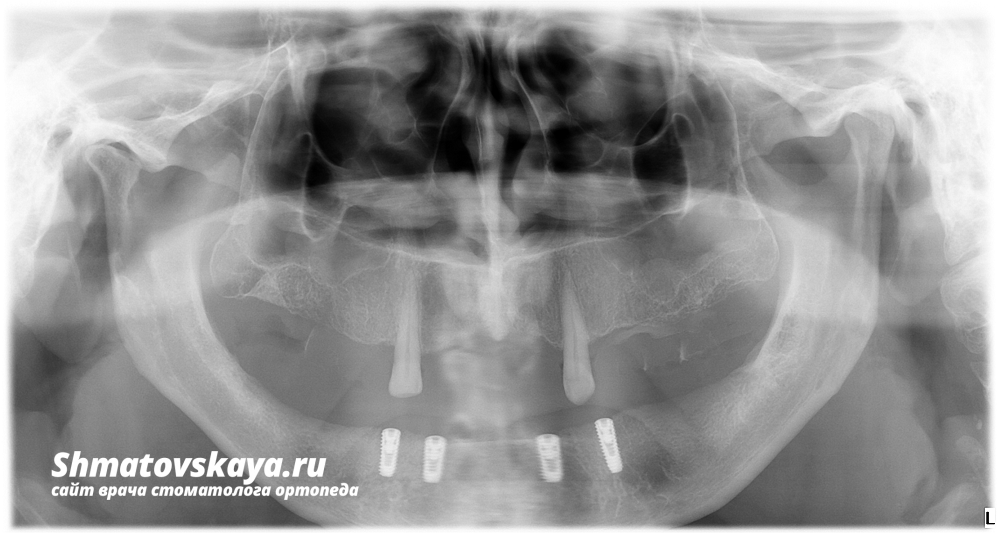

Рентген снимок ОПТГ

На нижней челюсти отсутствуют все зубы. На верхней челюсти имеются клыки (13 и 23 зубы). Пациент пользуется полным съёмным пластиночным протезом на нижней челюсти и частичным пластиночным протезом на верхней челюсти с кламмерной фиксацией.

1. На нижнюю челюсть были установлены 4 имплантата системы Osstem.